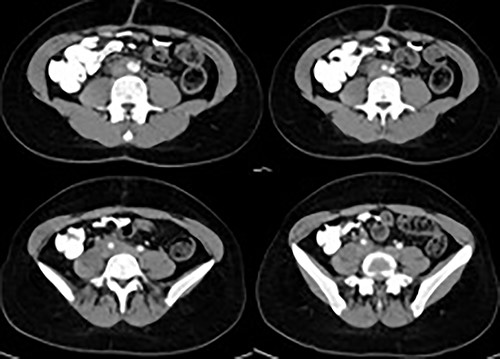

A 22-year-old with a history of polycystic ovaries and mesenteric resection, 6 months ago, was hospitalized for flatulence, indigestion, vomiting, anorexia and weight loss. He underwent computed tomography (CT) of the abdomen (Fig. 1), where a mass encloses the abdominal aorta and the arterial and venous axes as well as the right ureter. During the operation, a peritoneal tumor mass was found, which surrounds the lower part of the abdominal aorta and the pelvic vessels. A rapid biopsy was sent and the response to Castleman’s disease surprised the surgical team, who requested a vascular surgeon to be present. The mass was removed from the vessels, followed by appendicectomy and resection of the aortic lymph nodes (Fig. 2). The patient had a normal postoperative course and left the hospital on the fourth day after the operation.

CT of the abdomen revealed a mass encloses the abdominal aorta and the arterial and venous axes as well as the right ureter.

During the operation, the mass was detached from the abdominal aorta and common iliac arteries and veins.